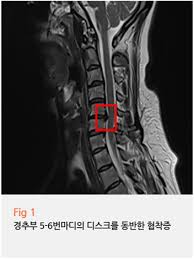

5. 오른쪽 가슴 통증과 호흡기 질환

호흡기 질환도 오른쪽 가슴 통증의 원인 중 하나입니다. 기침이나 호흡 곤란이 동반되는 경우, 폐렴이나 기흉과 같은 문제가 있을 수 있습니다. 이러한 증상이 나타나면 흉부 X-ray나 폐 CT 검사를 통해 호흡기 상태를 점검해야 합니다. 호흡기 문제가 확인된다면 적절한 치료를 통해 오른쪽 가슴 통증을 완화할 수 있습니다.